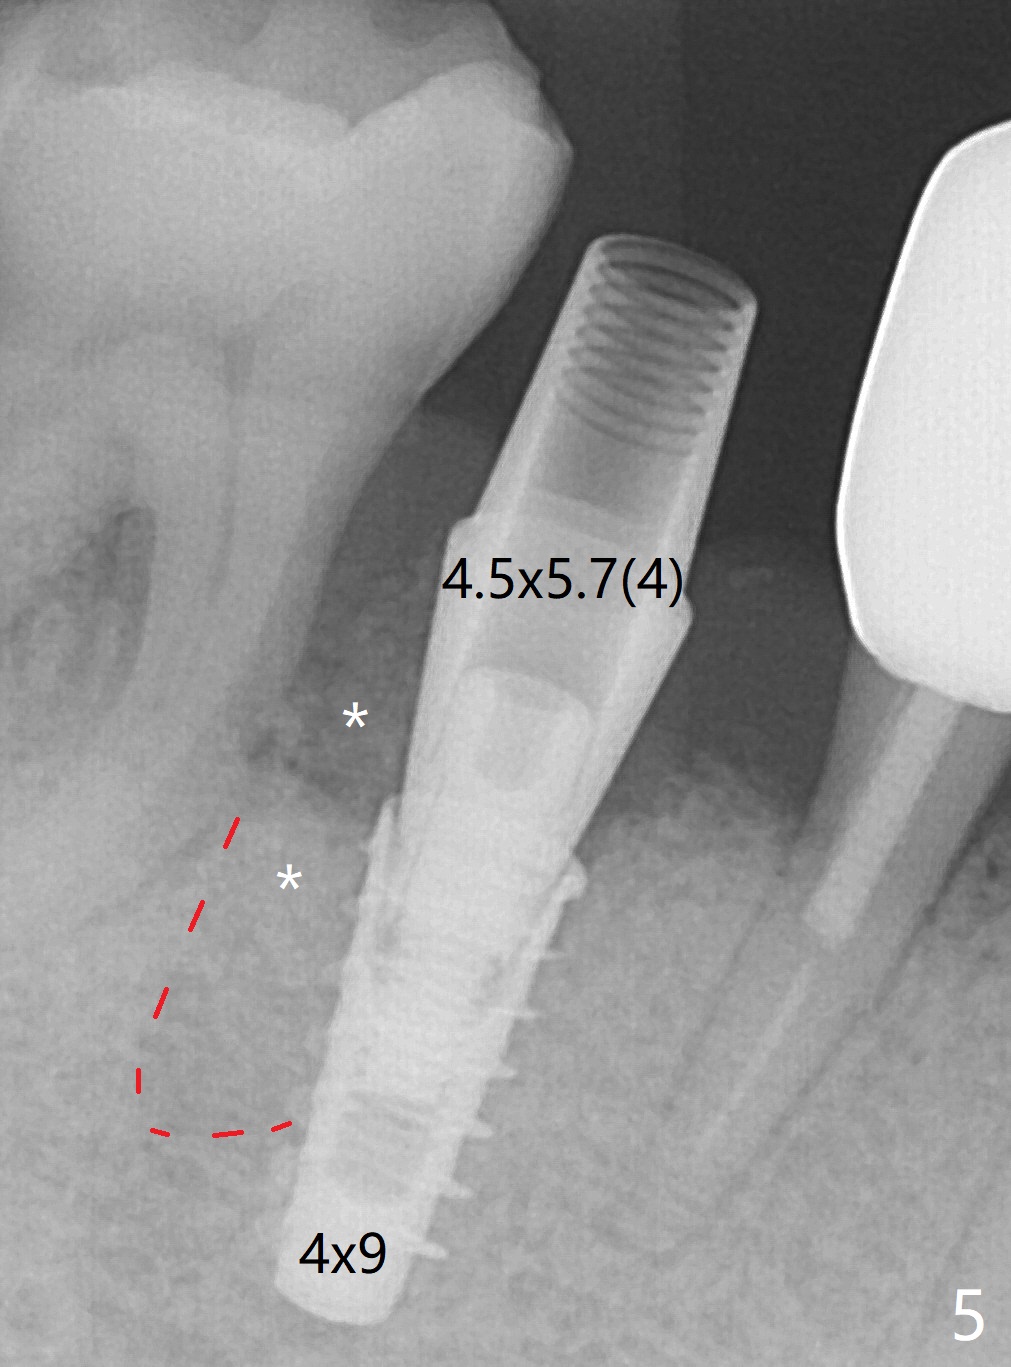

The tooth #29 is easily extracted with granulation tissue attached to the apex (Fig.1,2). The buccal plate is low. Initial osteotomy is established in the mesial slope of the socket for 13 mm subgingival (Fig.3 red dashed line). After adjustment of the osteotomy position and use of Magic Drills 2.8 and 3.3 mm for 15 mm subgingival, a 4x9 mm dummy implant is placed 2 mm subgingival (Fig.4). Final implant (Fig.5: 4x9 mm; red dashed line: socket) is placed 4 mm subgingival (supracrestal buccal; infracrestal lingual); Vanilla graft placed buccodistal (*). With placement of a 4.5x5.7(4) mm abutment (Fig.5), an infraocclusal immediate provisional (Fig.6 P) is fabricated to maintain the interdental papillae. One month later, the abutment dislodges. The patient insists upon no provisional so that he can masticate on the right side, since there is no functional molars on the left side. The implant appears to have osteointegrated 5 months postop (Fig7). The crown is loose 2.5 months post cementation (8.5 months postop); there is bone loss around the implant (Fig.8 *). Vanilla graft is placed after implant removal (Fig.9); in fact the neighboring teeth also have mobility (including periapical radiolucency at #30 (Fig.9 *)).